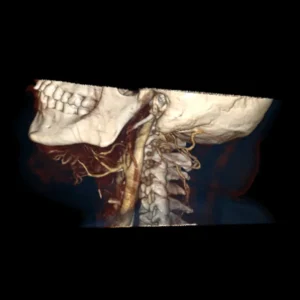

Cirugía ortognática (asimetrías faciales)

Corrección quirúrgica de deformidades óseas en mandíbula y maxilares para mejorar estética, mordida y respiración.

La cirugía ortognática, del griego orthos, «recto» y gnathos, «mandíbula», es una intervención quirúrgica que se encarga de corregir las deformidades dento-craneo-maxilofaciales mediante movimientos óseos maxilares y mandibulares, para lograr el equilibrio perfecto entre todas las características faciales del paciente.

Este tipo de alteraciones faciales aparecen en la fase de crecimiento de los pacientes, se estabilizan al final de la misma, y pueden causar problemas como apnea del sueño, trastornos de la ATM, problemas de maloclusión o falta de armonía esquelética, entre otros.